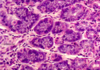

parotid gland

almost all serous acini

long intercalated ducts

myoepithelial cells

many plasma cells

excretory ducts go from simple columnar epithelim to pseudostratified to stratified columnar